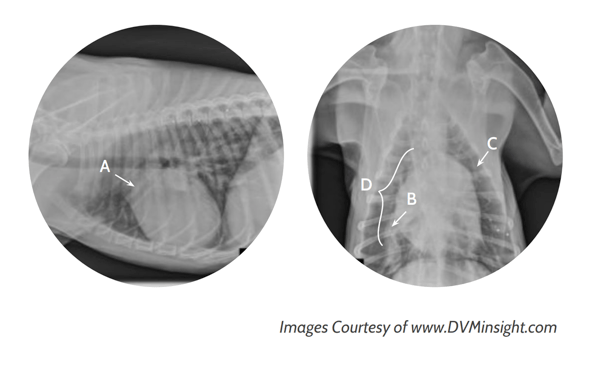

The main life-threatening complication of any heartworm treatment, and of heartworm disease in general, is pulmonary thromboembolism (PTE). Any time an adult worm dies, the dead worm travels into the peripheral pulmonary vessels and puts the patient at risk for PTE.Dogs receiving adulticide experience the death of all of their adult worms within a period of a couple of months, allowing the veterinarian and pet owner to take steps to minimize PTE risks during this time (prednisone administration, exercise restriction, careful monitoring). Dogs receiving slow-kill treatment experience unpredictable worm death over a period of several years, making it far more challenging to minimize the risk of complications.Heartworm disease also causes permanent damage within the heart and lungs. Studies have shown that radiographic signs of heartworm disease develop and progress even while a dog is on slow-kill treatment.(1) This is in contrast to adulticide treatment, in which the damage is halted quickly.Caption: Radiographs show enlargement of the pulmonary arteries (A, B), main pulmonary artery bulge (C), and “reverse D” shape (D).]Myth: Slow-kill heartworm treatment allows the dog to avoid activity restriction.